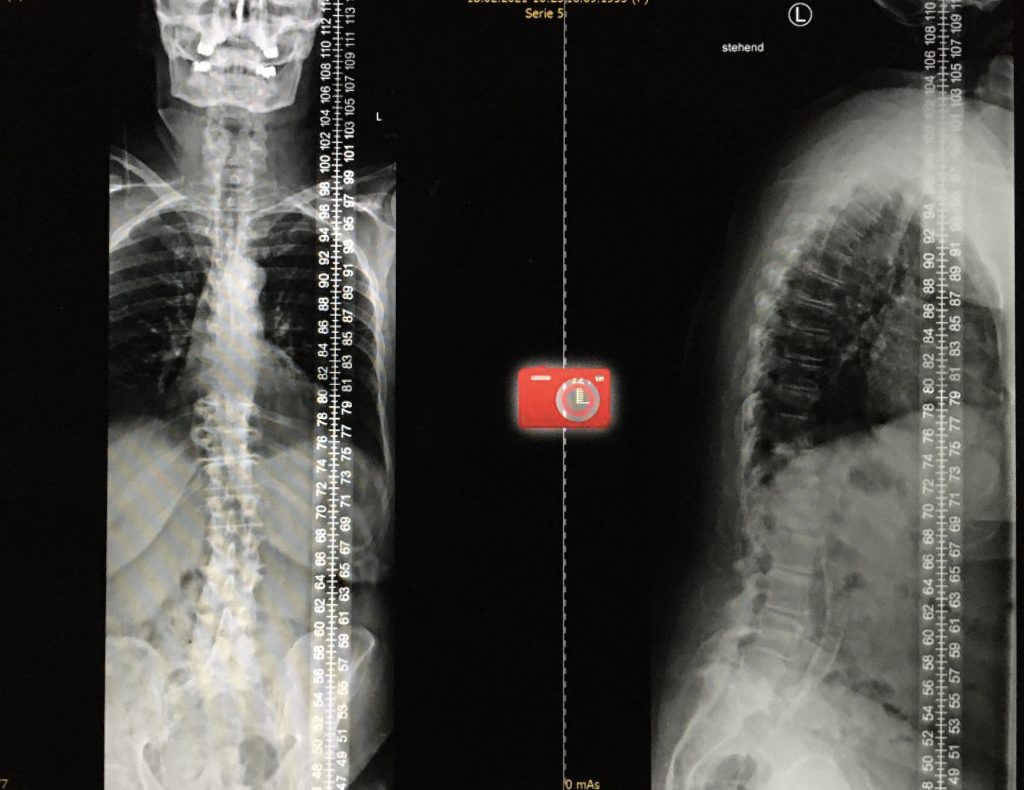

Conseguir una correcta alineación del raquis puede llegar a necesitar cirugía. La cirugía tiene dos metas principales: detener el avance de la curva y corregir la deformidad espinal.

La cirugía en las llamadas idiopática del adolescente se indica para los casos de escoliosis de más de 40°, o para pacientes que no responden al corsé. La cirugía generalmente tiene dos metas principales: detener el avance de la curva y corregir la deformidad espinal.

Habitualmente la escoliosis se corrige por vía posterior con monitorización de la función nerviosa durante la intervención (neurofisiología intraoperatorios). Se colocan tornillos en las vértebras y se acoplan con barras de metal a cada lado de la columna, tras realizar las maniobras de corrección necesarias, se consigue de este modo estabilizar el raquis y una columna vertebral más equilibrada y de aspecto más recta. Lo más habitual es utilizar técnicas de fusión ósea mediante el aporte de injerto de hueso del propio paciente o material sustitutivo al lecho quirúrgico. Este proceso se denomina fusión espinal. Las barras de metal acopladas a la columna vertebral aseguran que la columna permanezca recta mientras se produce la fusión espinal.